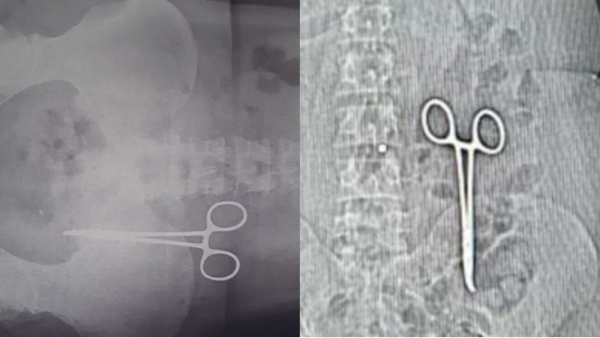

कई दिन से पेट दर्द था, पता चला दो साल पहले ऑपरेशन के समय डॉक्टरों ने पेट में कैची छोड़ दी थी

Bhind News: मध्य प्रदेश के भिंड में सरकारी अस्पताल के डॉक्टरों की बड़ी लापरवाही सामने आई है। डॉक्टरों ने कैंसर के ऑपरेशन के दौरान महिला के पेट में कैंची छोड़ दी थी। इससे महिला काफी परेशान रही। परिजनों को इसका पता दो साल बाद चला है।

दरअसल, 44 वर्षीय महिला का दो साल पहले ग्वालियर के कमला राजा अस्पताल में ऑपरेशन हुआ था। जिसके बाद से उसके पेट में दर्द हो रहा था।शुक्रवार देर शाम जब सीटी स्कैन कराया गया तब इसका खुलासा हुआ है।

सौंधा गोहद की रहने वाली कमला बाई ने बताया कि पिछले 2 वर्ष पहले से पेट दर्द से परेशान थीं। बार-बार जांच और दवाओं के बावजूद कोई राहत नहीं मिली। आखिरकार दर्द बढ़ने पर भिंड जिला अस्पताल में सीटी स्कैन करवाया।

स्कैन प्रभारी सतीश शर्मा ने बताया कि स्कैन करते ही पेट में एक धातु की वस्तु दिखाई दी,जो बाद में कैंची निकली।

कमला बाई के अनुसार 20 फरवरी 2022 को ग्वालियर के कमला राजा अस्पताल में पेट में कैंसर की गांठ का ऑपरेशन हुआ था। इस दौरान डॉक्टरों ने लापरवाही से ऑपरेशन के बाद पेट में कैंची छोड़ दी। तब से लगातार दर्द से परेशान थीं, लेकिन कोई भी डॉक्टर असली समस्या को नहीं पकड़ पाया।